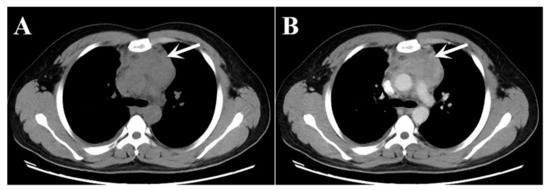

A 23-year-old man presented with a 5-day history of right-sided chest pain. The physical examination displayed no obvious abnormalities. His laboratory tests revealed increased C-reactive protein (15.36 mg/L; normal range: 0–3 mg/L) and hyperglobulinemia (40.7 mg/L; normal range: 20–40 mg/L). The chest CT (Figure 1) and 18F-PET/CT (Figure 2) were used to assess the locoregional extent and clinical stage of the disease, respectively. CT examination showed a soft tissue mass in the anterior mediastinum measuring 8.5 × 5.0 cm² approximately with unclear boundaries. The plain CT value was 40 HU, and the enhanced CT value was 87 HU. This patient was initially diagnosed with lymphoma or thymoma by experienced radiologists. Subsequently, PET/CT showed abnormally high FDG uptake (SUVmax: 8.96) in this lesion. No other abnormal 18F-FDG-avid lesion was observed.

Figure 1.

(A) Plain CT image; and (B) enhanced CT image present an abnormal soft tissue lesion in the anterior mediastinum of a 23-year-old young man (white arrows).